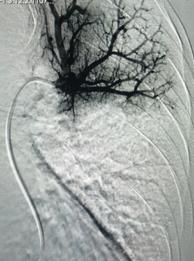

經(jīng)皮肺動脈造影

經(jīng)綜合評估并與家屬充分溝通后,局麻下行肺動脈造影,提示左肺動脈主干及左肺下葉動脈閉塞,立即予以經(jīng)皮肺動脈栓塞導(dǎo)管介入碎栓溶栓術(shù)。在心內(nèi)科韋鋒主任、郭良玉主治醫(yī)師及成婷護(hù)師的默契配合下,爭分奪秒順利完成手術(shù)。術(shù)后即刻復(fù)查肺動脈造影示左肺動脈主干及左肺下葉動脈恢復(fù)血流,生命體征穩(wěn)定,指脈氧恢復(fù)至100%。經(jīng)過精心治療與護(hù)理,目前患者已康復(fù)出院。